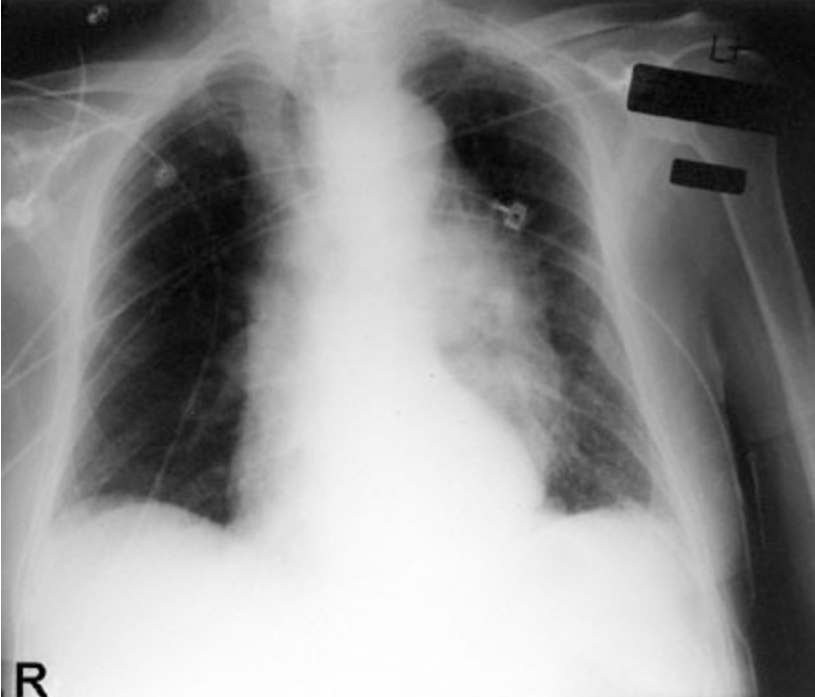

A previously healthy 57-year-old man is brought to the emergency department immediately after being involved in a head-on motor vehicle collision. He was the driver and was wearing a seat belt with a shoulder strap. On arrival, he is alert and oriented to person, place, and time. He says that he does not think he had loss of consciousness but feels sore all over his body. His temperature is 36.7°C (98°F), pulse is 100/min, respirations are 14/min, and blood pressure is 140/70 mm Hg. Pulse oximetry on 2 L/min of oxygen via nasal cannula shows an oxygen saturation of 99%. Physical examination and an ECG show no abnormalities. A chest x-ray is shown. Which of the following is the most likely diagnosis?